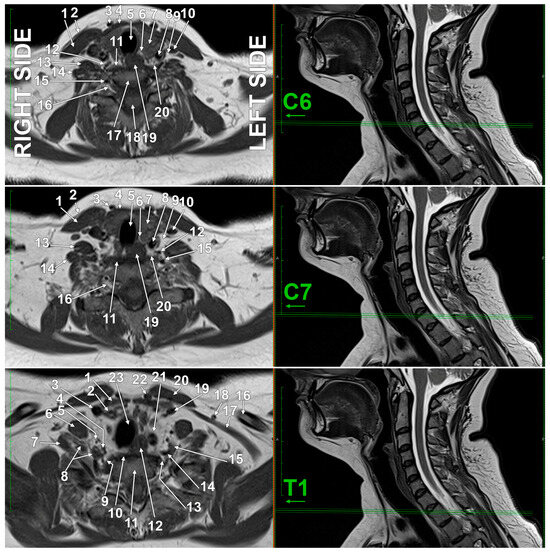

Anatomy, Imaging, and Clinical Significance of the Cervicothoracic (Stellate) Ganglion

Background/Objectives: The stellate ganglion (SG), formed by the fusion of the inferior cervical and first thoracic sympathetic ganglia in approximately 80% of individuals, plays crucial roles in cardiac innervation, pain management, and autonomic regulation. This review examines the anatomical variations, histological structure, [...] Read more.

Background/Objectives: The stellate ganglion (SG), formed by the fusion of the inferior cervical and first thoracic sympathetic ganglia in approximately 80% of individuals, plays crucial roles in cardiac innervation, pain management, and autonomic regulation. This review examines the anatomical variations, histological structure, clinical applications, and therapeutic implications of the SG and stellate ganglion block (SGB), presenting original high-resolution magnetic resonance imaging (MRI) evidence of SG visualization, an underutilized approach in autonomic nervous system research. Methods: We conducted a comprehensive literature review of anatomical, physiological, and clinical studies on the SG, incorporating original anatomical dissections and high-resolution MRI. Contemporary research on SGB applications, complications, and mechanisms of action was analysed and correlated with imaging characteristics. Results: The SG demonstrates significant anatomical variability, including the presence of intermediate ganglia, accessory nerve pathways, and variable relationships with surrounding vascular structures. Our original MRI imaging consistently identified the SG at the thoracic inlet, anterior to the neck of the first rib, lateral to the longus colli muscle, and posterior to the vertebral artery, demonstrating that advanced imaging can reliably visualize this critical autonomic structure and its anatomical variants. Histologically, it contains typical sympathetic architecture, comprising postganglionic neurons, satellite glial cells, and specialized SIF cells that modulate ganglionic transmission. SGB shows therapeutic efficacy across diverse conditions, including cardiac arrhythmias, chronic pain syndromes, post-traumatic stress disorder, sleep disorders, and immune dysfunction. The procedure’s mechanisms involve both direct sympathetic blockade and complex neuroimmune pathways that affect central autonomic centers and lymphoid organs. Complications include vascular injury, pneumothorax, and nerve blocks affecting the recurrent laryngeal and phrenic nerves. Conclusions: The SG represents a critical autonomic structure with expanding clinical applications. This work advances the field by demonstrating that high-resolution MRI can consistently and non-invasively visualize the SG and its anatomical variations, knowledge previously mostly limited to cadaveric studies. Understanding these imaging-defined anatomical variations is essential for optimizing therapeutic interventions. Advanced imaging guidance integrated with comprehensive anatomical knowledge is crucial for maximizing efficacy while minimizing complications in stellate ganglion block procedures. Full article

Show Figures

Figure 1